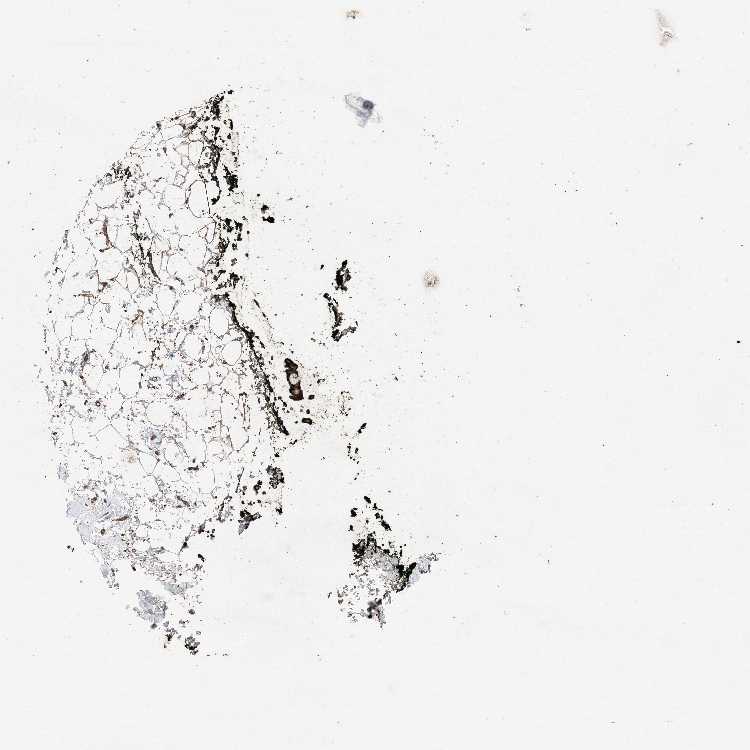

SOFT TISSUE 2 - Antibody stainingi

Antibody staining in the annotated cell types in the current human tissue is reported as not detected, low, medium, or high, based on conventional immunohistochemistry profiling in selected tissues. This score is based on the combination of the staining intensity and fraction of stained cells.

Each image is clickable and will lead to virtual microscopy that enables deeper exploration of all samples and also displays staining intensity scores, fraction scores and subcellular localization as well as patient and tissue information for each sample.

Antibody HPA034652Antibody HPA034653Antibody CAB034347

Chondrocytes Medium-High

Fibroblasts MediumHighMedium

Peripheral nerve Not detectedLowMedium